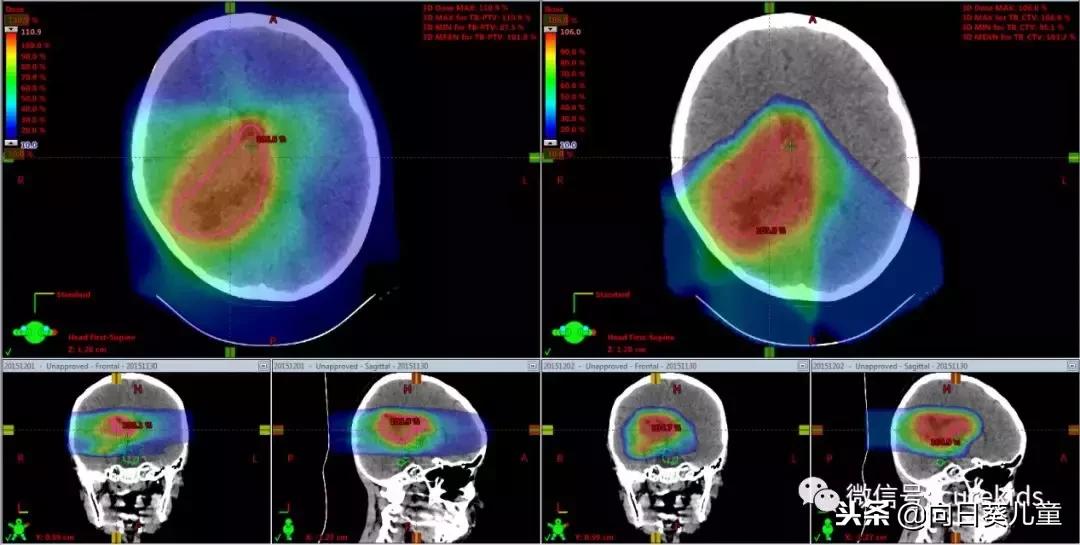

这是我们三年前治疗的一个脑部脉络丛癌病例。刚开始做的是全脑全脊髓治疗,后来针对瘤床做了最后的巩固治疗计划。

从这里可以看到使用多角度光子线治疗,整个脑部都在射线范围里;使用质子线,就是从后面三个角度,把脑部前面完整保护起来,完全没有放射性的影响。

而用光子线,脑部前面还是有一些中、低剂量的射线要经过。